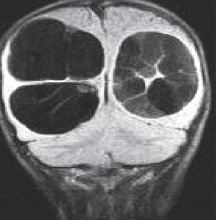

Эпидермоидные кисты (эпидермоиды) - доброкачественные врождённые образования. Они происходят из эктопических эпидермальных клеток и развиваются в период закрытия, в 3-5 нед. эмбриогенеза, как следствие неполного разделения нейрональной и покровной эктодермы. Частота составляет около 1% от внутричерепных образований. Обычно диагностируются в возрасте 25 - 45 лет. Локализация эпидермоидов может быть любой, но типичная - мосто-мозжечковый угол (третье по частоте образование этой области), предмостовая цистерна, параселлярная область, четверохолмие и желудочковая система, очень редко в полушариях, спинном мозге и интрадиплоидно. Растут они интра- или экстрадурально, экспансивно, медленно, сдавливая ствол мозга, внутричерепные нервы, но не разрушая кость. Иногда захватывают сосуды и нервы. По характеру роста их можно отнести к опухолевидным образованиям. Вокруг эпидермоидов нередко развивается асептическое воспаление, а при разрыве содержимое (жир, кератин) прорывается в ликворные пространства. Клинические проявления зависят от локализации и масс-эффекта.

При МРТ головного мозга картина неспецифическая и зависит от содержимого кисты. Если она не содержит жира, то имеет ликворную интенсивность сигнала . В таком случае эпидермоидная киста трудно отличима от арахноидальной, хотя, как правило, не столь однородная. На МРТ типа FLAIR и диффузионно-взвешенных МРТ изображениях содержимое эпидермоидов светлее ликворного. Жировое содержимое, такие эпидермоиды еще называют холестеатомой, приводит к высокому сигналу на Т1-взвешенных МРТ головного мозга. Видимо, он обусловлен липидами, но не холестеролом. На Т2-взвешенных МРТ головного мозга он менее интенсивен чем ликвор. Контуры эпидермоидов всегда четкие. Холестеатомы составляют всего 3-5% от эпидермоидов. В 15-20% случаев встречается кальцификация по переферии кисты. Редко наблюдается контрастирование стенок.

МРТ головного мозга. Т1-взвешенные корональная и сагиттальная МРТ. Эпидермоидная киста левой височной доли.